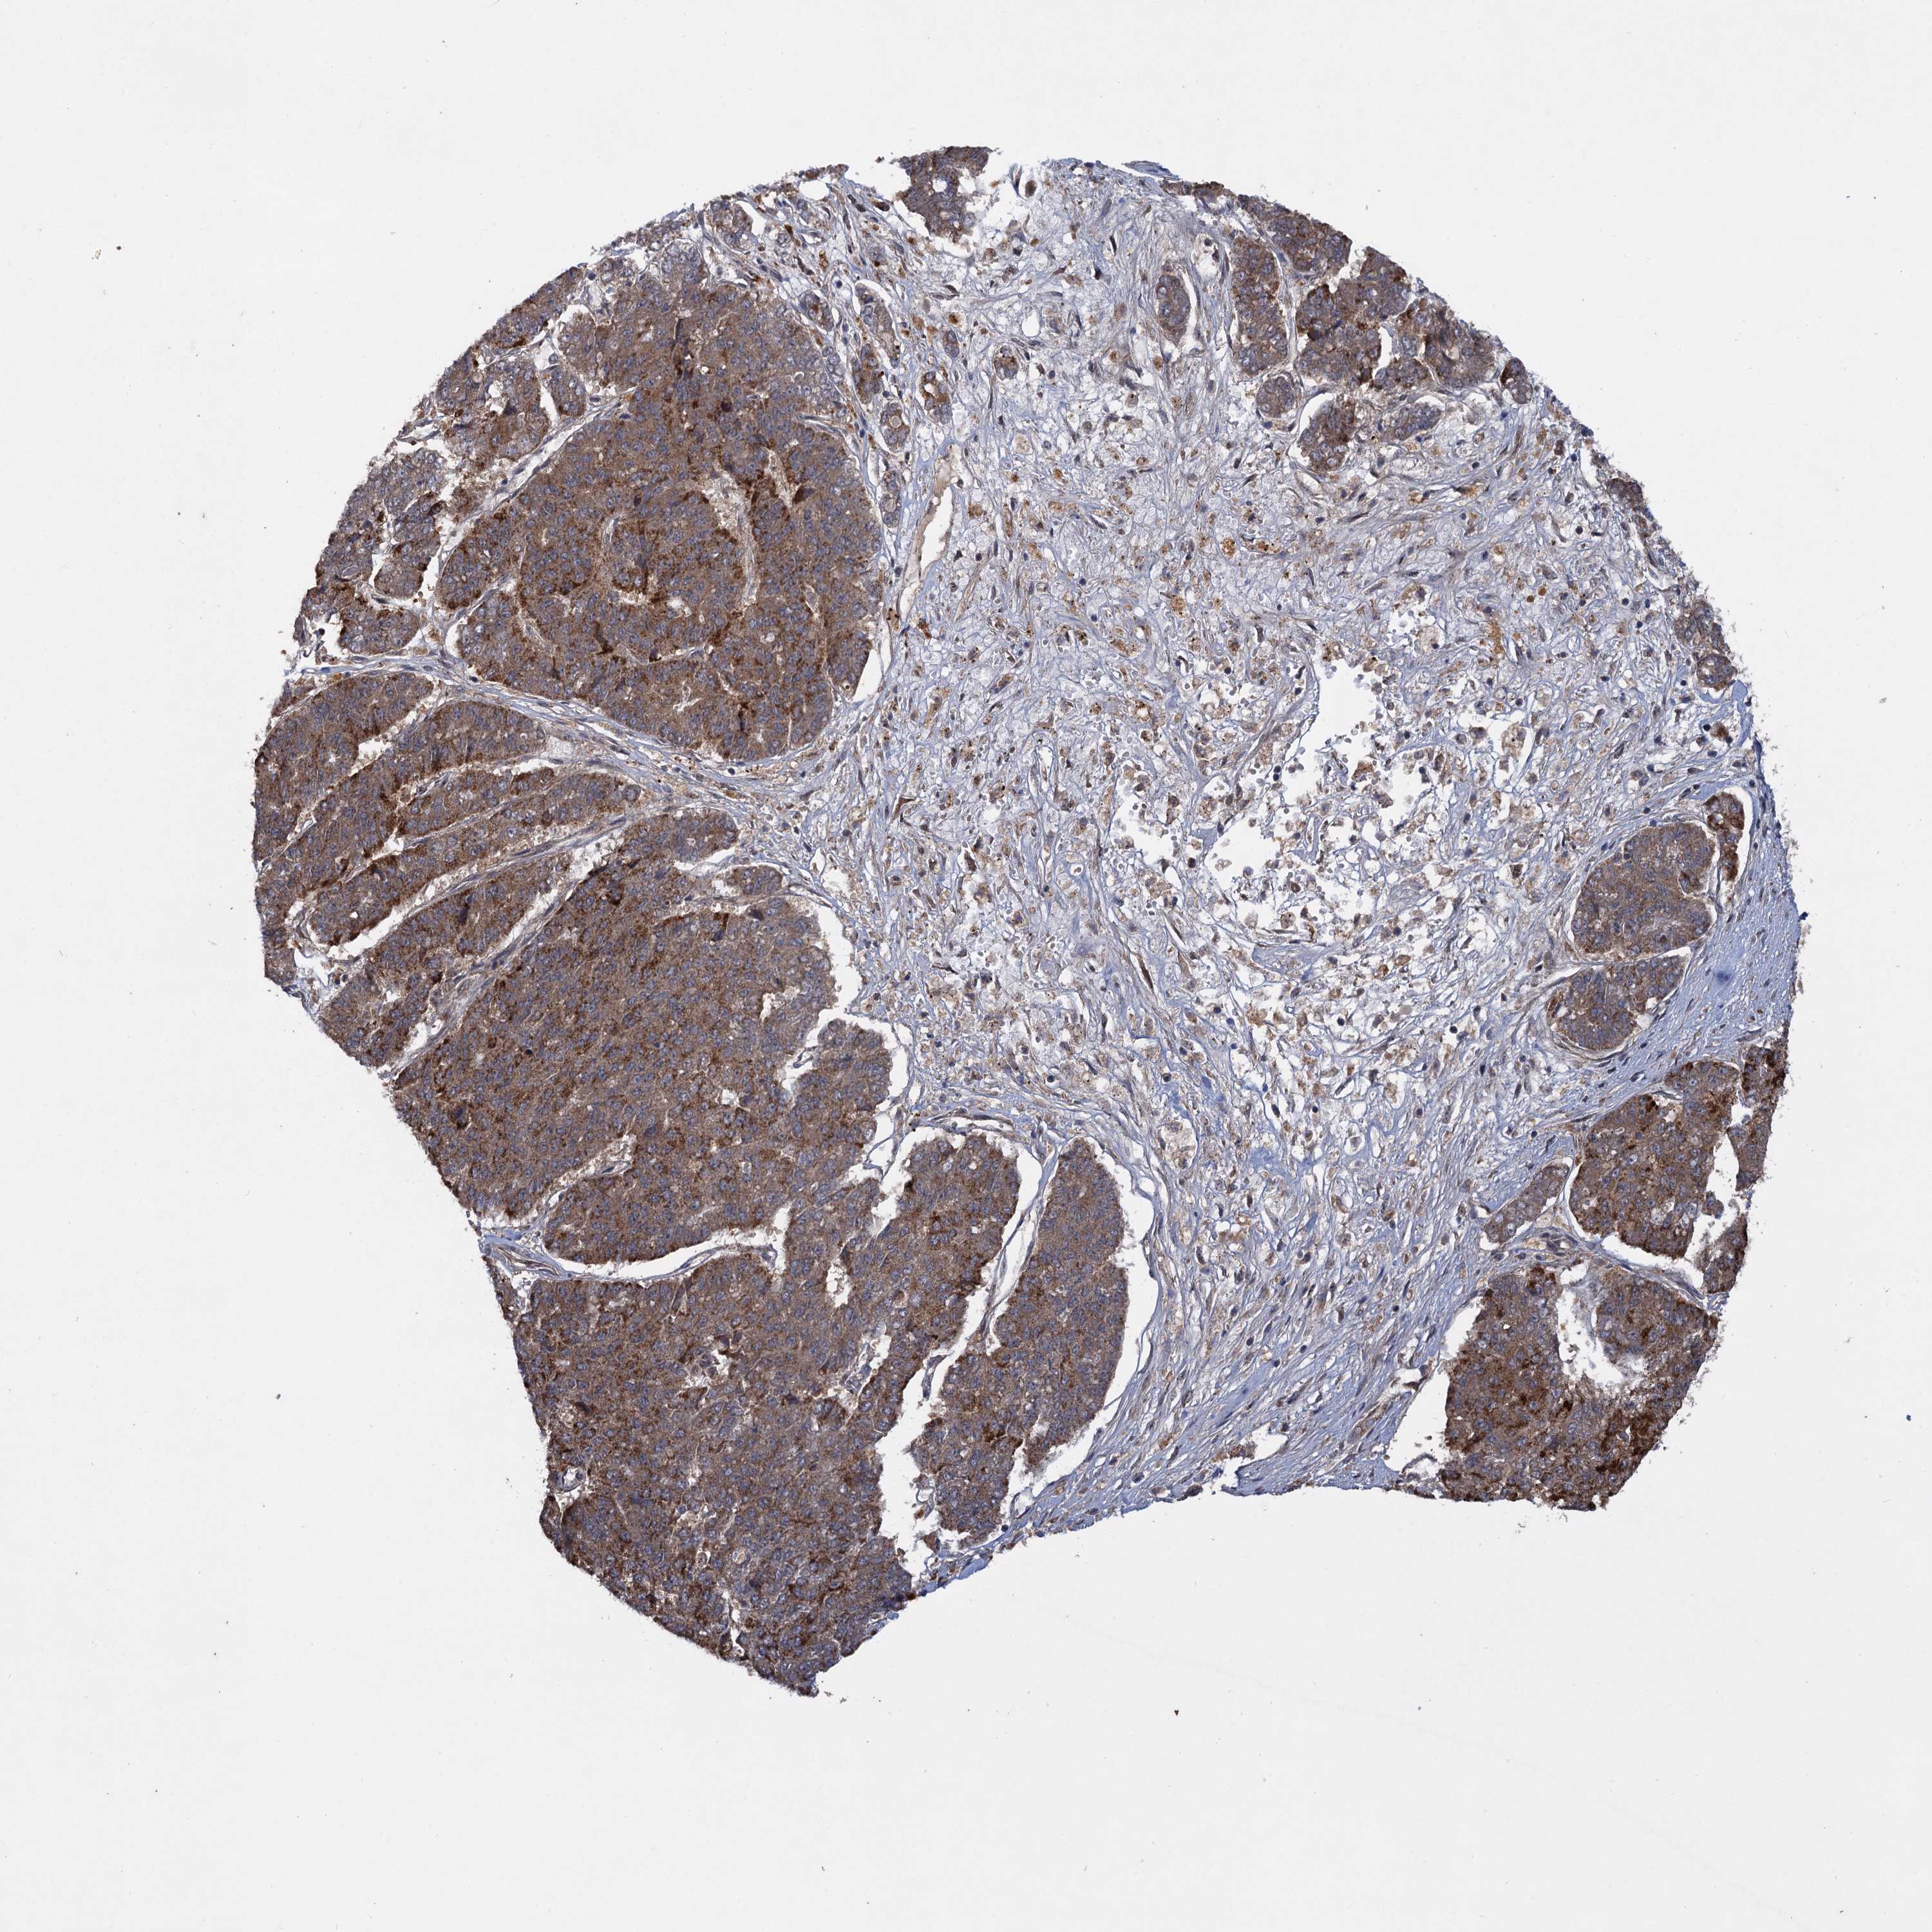

PANCREATIC CANCER - Protein expressioni

A mouse-over function shows sample information and annotation data. Click on an image to view it in a full screen mode. Samples can be filtered based on level of antibody staining by selecting one or several of the following categories: high, medium, low and not detected. The assay and annotation is described here.

Note that samples used for immunohistochemistry by the Human Protein Atlas do not correspond to samples in the TCGA dataset.

Antibody stainingi

Antibody staining in the annotated cell types in the current human tissue is reported as not detected, low, medium, or high, based on conventional immunohistochemistry profiling in selected tissues. This score is based on the combination of the staining intensity and fraction of stained cells.

Each image is clickable and will lead to virtual microscopy that enables deeper exploration of all samples and also displays staining intensity scores, fraction scores and subcellular localization as well as patient and tissue information for each sample.

Antibody HPA040601

Antibody HPA040652

Staining

High

Medium

Low

Not detected

Intensity

Strong

Moderate

Weak

Negative

Quantity

>75%

75%-25%

<25%

None

Location

Nuclear

Cytoplasmic/membranous

Cytoplasmic/membranous,nuclear

Adenocarcinoma, NOS